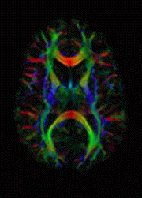

The imaging of this property is an extension of diffusion MRI. If a series of diffusion gradients (i.e. magnetic field variations in the MRI magnet) are applied that can determine at least 3 directional vectors (use of 6 different gradients is the minimum and additional gradients improve the accuracy for "off-diagonal" information), it is possible to calculate, for each voxel, a tensor (i.e. a symmetric positive definite 3×3 matrix) that describes the 3-dimensional shape of diffusion. The fiber direction is indicated by the tensor's main eigenvector. This vector can be color-coded, yielding a cartography of the tracts' position and direction (red for left-right, blue for superior-inferior, and green for anterior-posterior). The brightness is weighted by the fractional anisotropy which is a scalar measure of the degree of anisotropy in a given voxel. Mean diffusivity (MD) or trace is a scalar measure of the total diffusion within a voxel. These measures are commonly used clinically to localize white matter lesions that do not show up on other forms of clinical MRI.[58]

In 1990, Michael Moseley reported that water diffusion in white matter was anisotropic—the effect of diffusion on proton relaxation varied depending on the orientation of tracts relative to the orientation of the diffusion gradient applied by the imaging scanner. He also pointed out that this should best be described by a tensor.[31] Although the exact mechanism for the anisotropy has remained not completely understood, it became apparent in the early 1990s that this anisotropy effect could be exploited to map out the orientation in space of the white matter tracks in the brain, assuming that the direction of the fastest diffusion would indicate the overall orientation of the fibres, as first shown by D. Le Bihan (Douek et al.).[32] While the diffusion tensor concept was introduced in this article the authors used a simple approach in 2 dimensions (within the imaging plane) to obtain color maps of fiber orientation from the ratio between diffusion coefficients measured in the X and Y direction (Dyy/Dxx). This ratio (which is the tangent of the angle between the diffusion vector in the XY plane and the X axis) was displayed with a color scale (blue to green to red). The limitation of this "vector" approach was that Dxx and Dyy were only approximately known. Only the DTI method, which was introduced shortly after, gave access to all the components of the diffusion tensor (e.g., Dxy). In this seminal article, the authors also demonstrate that water diffusion is not really restricted, but merely hindered, even perpendicularly to the fibers, as the diffusion distance kept increasing with the diffusion time. Aaron Filler and colleagues reported in 1991 on the use of MRI for tract tracing in the brain using a contrast agent method but pointed out that Moseley's report on polarized water diffusion along nerves would affect the development of tract tracing.[33] A few months after submitting that report, in 1991, the first successful use of diffusion anisotropy data to carry out the tracing of neural tracts curving through the brain without contrast agents was accomplished.[29][34][35] Filler and colleagues identified both vector and tensor based methods in the patents in July 1992,[35] before any other group, but the data for these initial images was obtained using the following sets of vector formulas that provide Euler angles and magnitude for the principal axis of diffusion in a voxel, accurately modeling the axonal directions that cause the restrictions to the direction of diffusion:

The first color maps of white matter fiber orientation using diffusion MRI (Douek et al. 1991) [1]